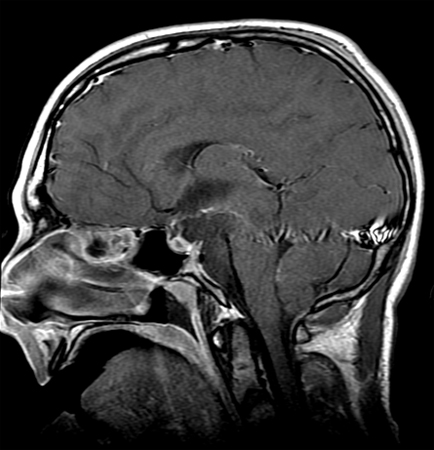

As endocrinopathies are common (both pre- and postoperatively), hormone replacement therapy is usually necessary, depending upon the specific endocrine deficiencies.[Figure caption and citation for the preceding image starts]: Craniopharyngioma: sagittal postcontrast MRIFrom the collection of Dr Marc C. Chamberlain [Citation ends].

[Figure caption and citation for the preceding image starts]: Craniopharyngioma (postoperative): sagittal postcontrast MRIFrom the collection of Dr Marc C. Chamberlain [Citation ends].